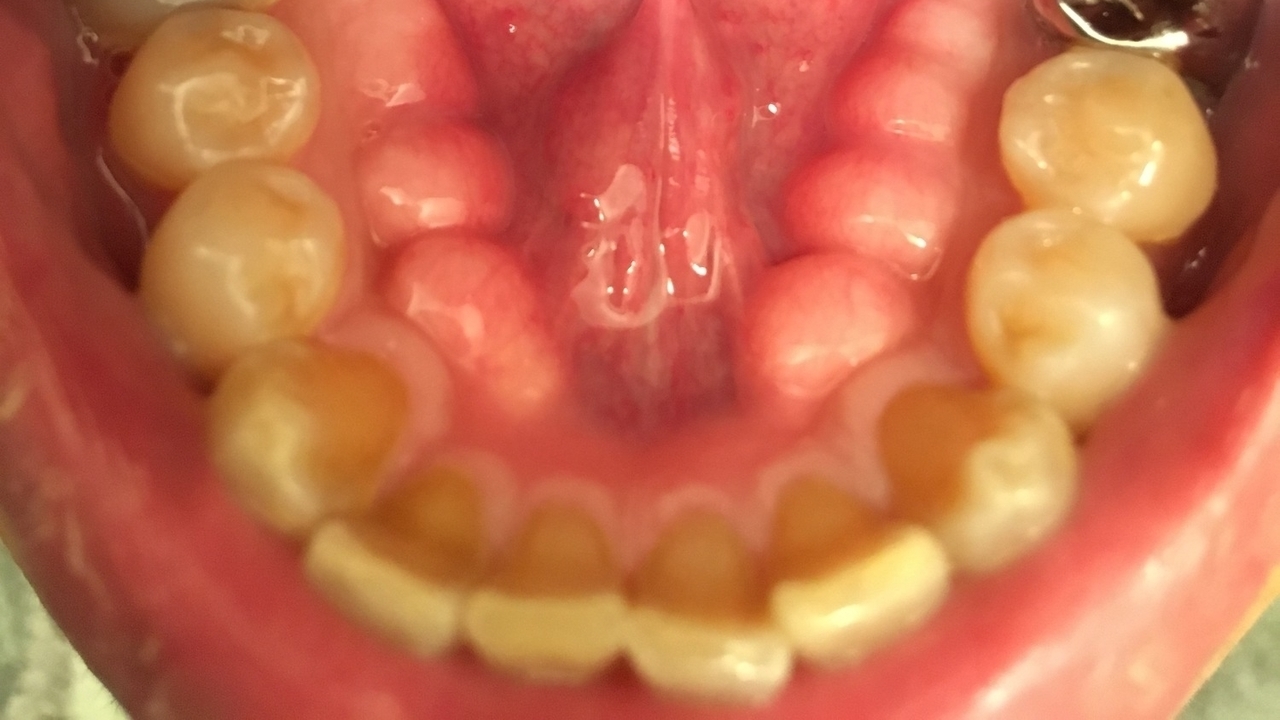

• 歯の噛む面がすり減ってきた

• 歯が削れる

まず、歯やあごに大きな負担がかかるとエナメル質(歯の表面の硬い層)が削れやすくなります。その結果、知覚過敏や虫歯のリスクが上がってしまいます。

最後に、歯の根元部分が楔状に欠けたように見える楔状欠損のリスクも見逃せません。強い噛みしめや歯ぎしりによって歯と歯茎の境目付近に力が集中し、少しずつ歯の表面が削れてしまいます。